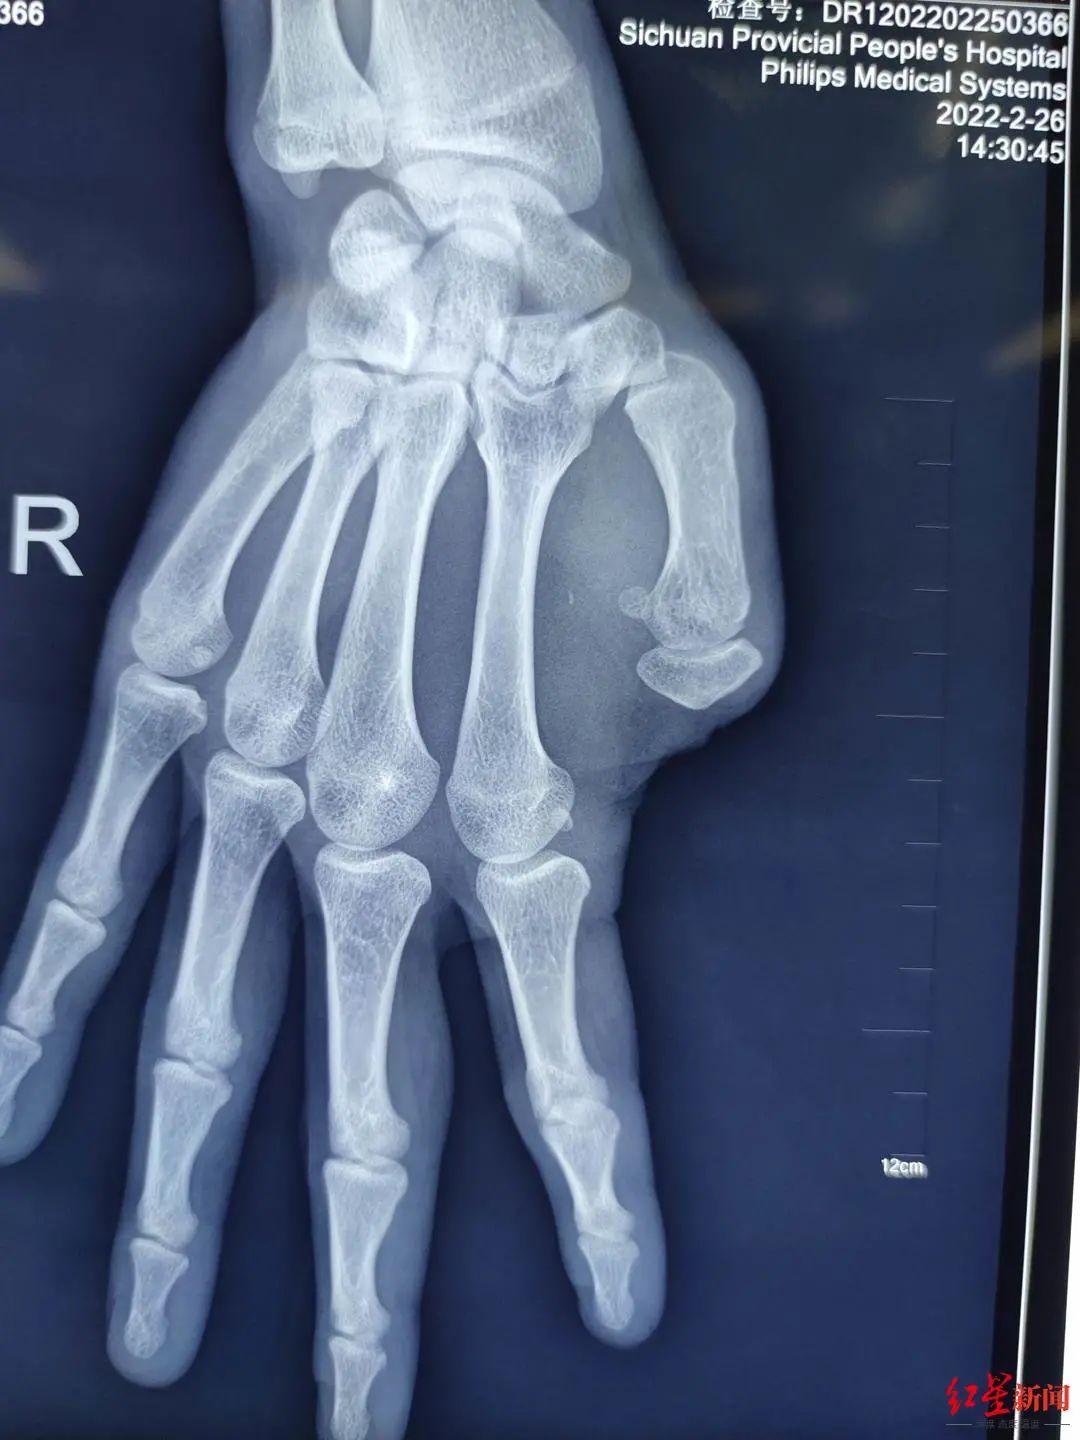

一周前,四川省人民医院骨科医生将他右脚大拇趾,移植到右手大拇指位置,弥补了他15年前丢失的大拇指。

小杨今年22岁,15年前,因意外缺失了右手大拇指。大拇指的缺失,不仅外观异于常人,更重要的是,无法使用右手写字,以及完成一系列精细动作,生活、学习受到影响。

常规的大拇指再造,一般选择足的第二趾。小杨大拇指属于Ⅲ度以内缺损,也可以选择足拇趾移植再造。

术前的手照片显示右手大拇指缺失